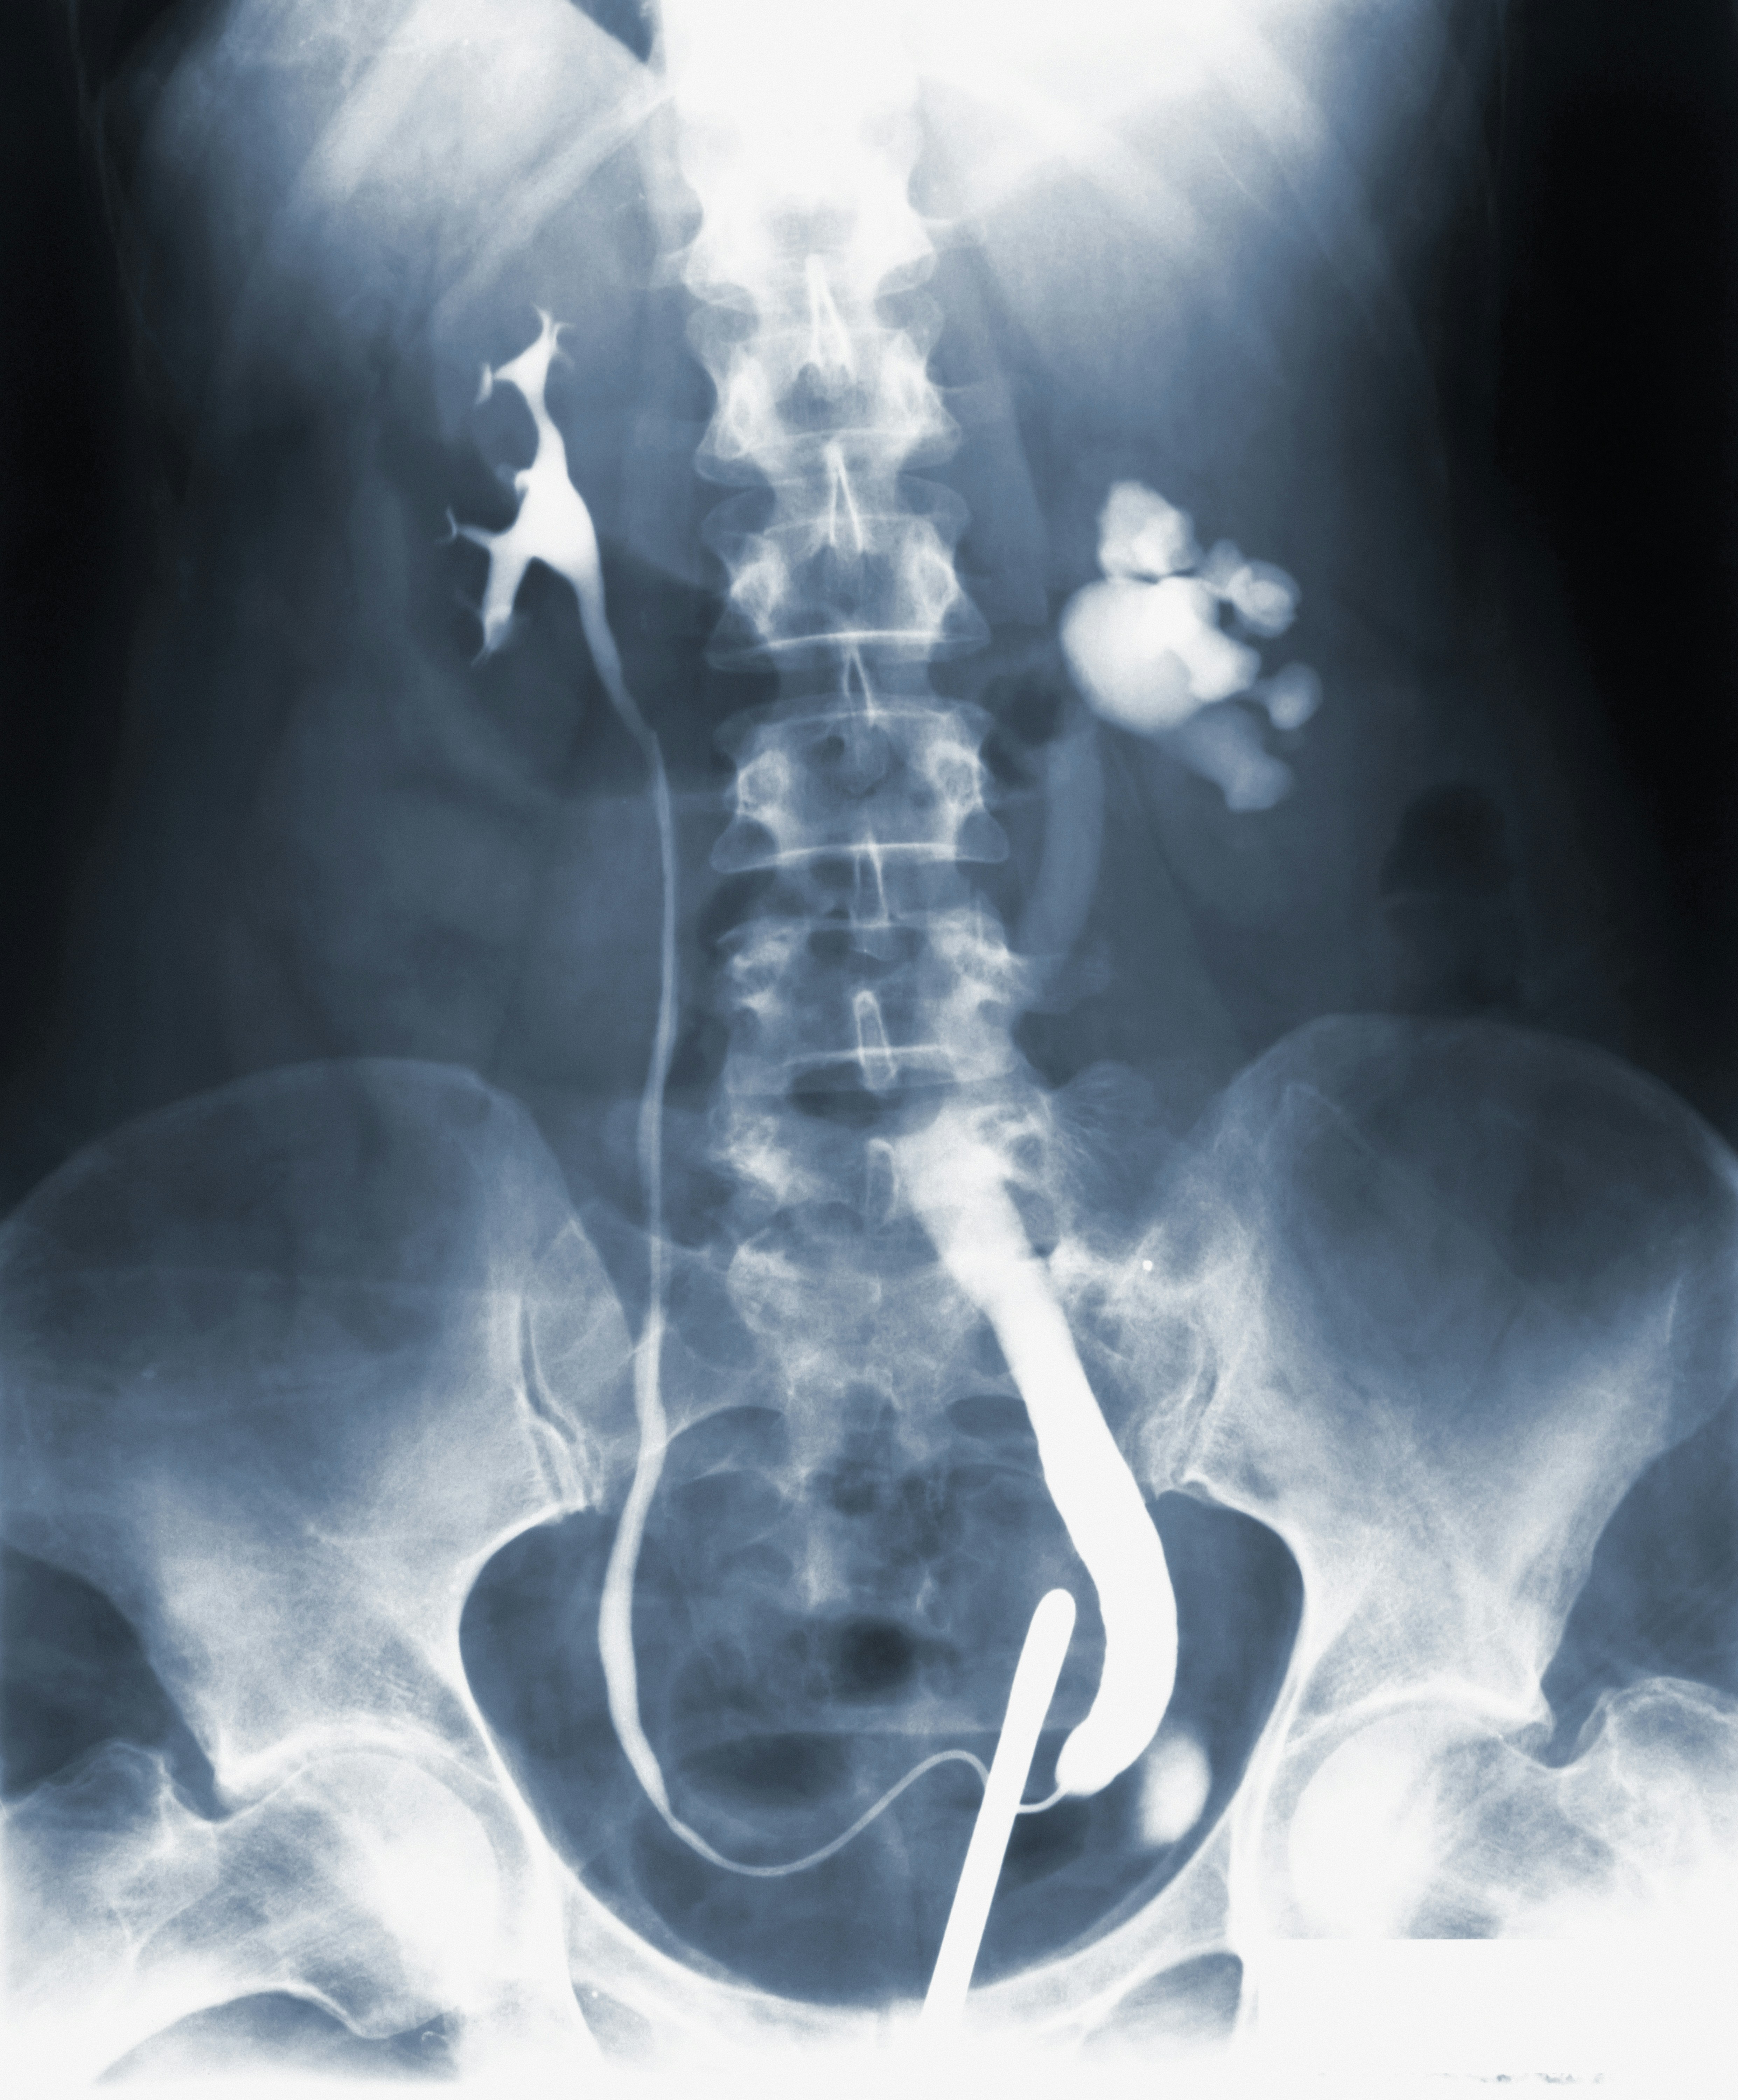

Co można zobaczyć na zdjęciu RTG brzucha?

Obraz uzyskany podczas badania RTG jamy brzusznej pozwala na ocenę wielu istotnych struktur anatomicznych. Najlepiej widoczne są kości, takie jak kręgosłup, żebra czy miednica, ponieważ skutecznie pochłaniają promieniowanie rentgenowskie. W przypadku tkanek miękkich, jak wątroba, śledziona czy nerki, ich zarys może być mniej wyraźny, jednak obecność gazów w przewodzie pokarmowym, płynów lub ciał obcych jest możliwa do rozpoznania na standardowym zdjęciu. RTG brzucha umożliwia także wykrycie patologicznych zmian, takich jak rozdęcia jelit, zwężenia czy obecność wolnego powietrza świadczącego o perforacji przewodu pokarmowego.

W niektórych przypadkach lekarz może zdecydować o zastosowaniu środka kontrastowego, który podawany jest doustnie, dożylnie lub doodbytniczo. Kontrast poprawia widoczność wybranych narządów i struktur, umożliwiając dokładniejszą ocenę przewodu pokarmowego lub układu moczowego. Dzięki temu łatwiej jest zidentyfikować takie zmiany jak niedrożność jelit, obecność kamieni nerkowych czy patologiczne nagromadzenie płynu w jamie brzusznej. Wskazania do użycia kontrastu ustalane są indywidualnie i zależą od podejrzeń klinicznych oraz celu diagnostycznego badania.

• RTG jamy brzusznej pozwala na szybkie wykrycie połkniętych ciał obcych, co jest szczególnie istotne u dzieci.

• Obecność wolnego powietrza pod przeponą na zdjęciu może wskazywać na perforację przewodu pokarmowego i wymaga pilnej interwencji.

• Badanie umożliwia ocenę rozkładu gazów w jelitach, co pomaga w rozpoznaniu niedrożności lub innych zaburzeń czynnościowych.

• W przypadku podejrzenia kamicy nerkowej RTG może uwidocznić złogi wapniowe w obrębie dróg moczowych.

Interpretacja zdjęcia rentgenowskiego wymaga doświadczenia i wiedzy specjalisty radiologa, który potrafi odróżnić zmiany fizjologiczne od patologicznych. W razie potrzeby, dla uzyskania pełniejszego obrazu klinicznego, można rozważyć wykonanie dodatkowych badań obrazowych, takich jak tomografia komputerowa czy ultrasonografia. Dzięki nowoczesnym rozwiązaniom teleradiologicznym opis zdjęć RTG może być dostępny dla lekarza prowadzącego już w krótkim czasie po wykonaniu badania.